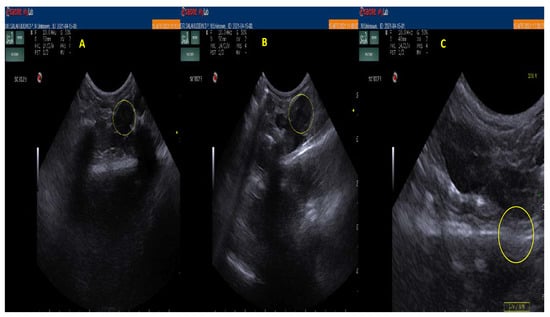

3.6. In Vivo Floating Study